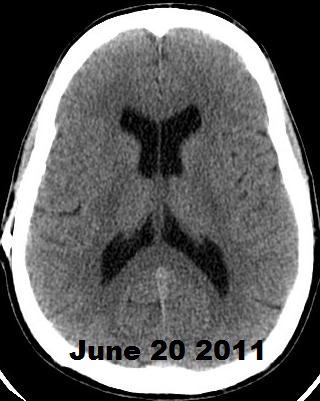

Below, are my CT images beginning on Jan. 17, 2011, where there is enlargement of the ventricles, followed by further enlargement on April 9, 2011, and what appears to be more enlargement on June 8, 2011, despite my May 23, 2011 revision. Then, there appears to be a slight decrease in ventricular enlargement on June 20, 2011, followed by normal size (almost too small) ventricles on July 23, 2011. We felt my ventricles came down in size too quickly, and began to raise the proGav setting over a period of two months, eventually up to 6, and rescanned me on Sept. 15, 2011. Those results indicated my ventricular enlargement had returned, so the proGav was returned to a lower setting of 2.

Under my CT images below, I list each of the proGAV's corresponding settings. It was initially set at 10 during surgery, with no improvement in complaints after one week, I asked that it be lowered to 7, and one week later to 5, then to 3, and finally to 0. During this period, almost every morning I awoke with a substantial headache that I assumed was due to increased ICP and underdrainage. On the June 20, 2011, CT we could finally see some decrease in the dilation of my ventricles, and determined the shunt to be working. But, we were still puzzled by the ongoing awaking a.m. headaches. For this reason, it was temporarily raised to a setting of 2, and then with no relief back down to 0. It remained at 0 for almost a month when the July 23, 2011 scan revealed normal sized ventricles.  Because of the relatively short period it took for my ventricles to come back to normal, we raised the proGAV gradually to 6, and back down to 2 after the Sept. 15, 2011 scan showed a return of ventriculomegaly.

June 8, 2011 proGAV  5/20    June 20, 2011 proGAV 3/20      July 23, 2011 proGAV 0/20    Sept. 15, 2011 proGav 6/20   Feb. 1, 2012 proGav 0/20